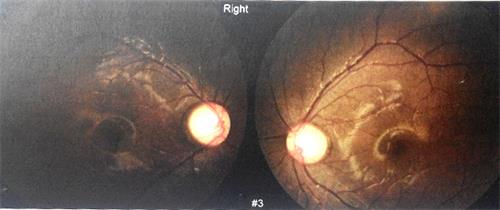

二零一二年四月,洪洪告诉我,他坐在第一排都看不见黑板上的字。于是五月份,我们再次来到华西医院进行检查。医生告诉我:“你家小孩的眼睛验光,300度也只能看到0.8,200度也是0.8,度数上不去。你带他做一个全面的检查。”下面这些就是当时做眼部OCT时照出来的图片:

图2~4:ODOCT图

最后医院诊断为双眼发育性青光眼。原来,洪洪歪着脑袋斜着看是因为眼底正前方可能被强光灼伤(见黄斑区),所以只能歪着脑袋才能正确聚焦。